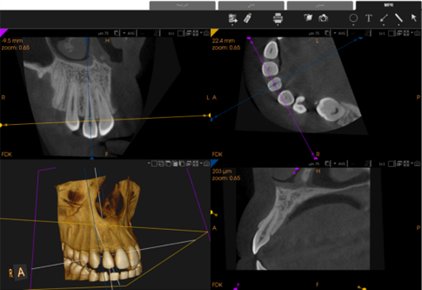

This study aimed to evaluate the morphology of maxillary lateral incisors in patients with unilateral palatally impacted canines compared to the contralateral side using cone beam computed tomography (CBCT) technique.

A cross-sectional study analyzed CBCT images of 70 patients (35 males and 35 females; mean age, 25.83 ± 9.27 years) with unilateral palatally impacted canines. The lateral incisor length, crown width, and colum angle were evaluated on both the impacted and non-impacted sides. Paired and independent t-tests were used for comparisons, and intraclass correlation coefficients (ICCs) were used to assess intra- and inter-examiner reliability. Statistical significance was set at P < 0.05.

The results revealed a statistically significant difference in lateral incisor length between the impacted side (21.81 ± 2.28 mm) and the non-impacted side (22.12 ± 2.03 mm). In contrast, crown width and collum angle did not show any significant differences. In the gender-based comparison, the lateral incisor length was significantly reduced in female participants (p = 0.006). All ICC values indicated excellent agreement (ICC > 0.9).

The lateral incisor was significantly shorter on the impacted side than on the non-impacted side, supporting its potential role as a clinical predictor of palatal canine impaction. In contrast, there were no significant differences in the crown width or colum angle of the lateral incisors.